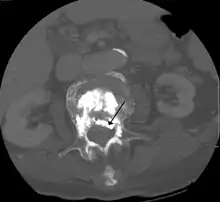

Some of the associated risks are from the leak of acrylic cement to outside of the vertebral body. Although severe complications are extremely rare, infection, bleeding, numbness, tingling, headache, and paralysis may ensue because of misplacement of the needle or cement. This particular risk is decreased by the use of X-ray or other radiological imaging to ensure proper placement of the cement.[2] In those who have fractures due to cancer, the risk of serious adverse events appears to be greater at 2%.[23]

The risk of new fractures following these procedures does not appear to be changed; however, evidence is limited,[17] and an increase risk as of 2012 is not ruled out.[25] Pulmonary cement embolism is reported to occur in approximately 2-26% of procedures.[26] It may occur with or without symptoms.[26] Typically, if there are no symptoms, there are no long term issues.[26] Symptoms do occur in about 1 in 2000 procedures.[22] Other adverse effects include spinal cord injury in 0.6 per 1000.[22]